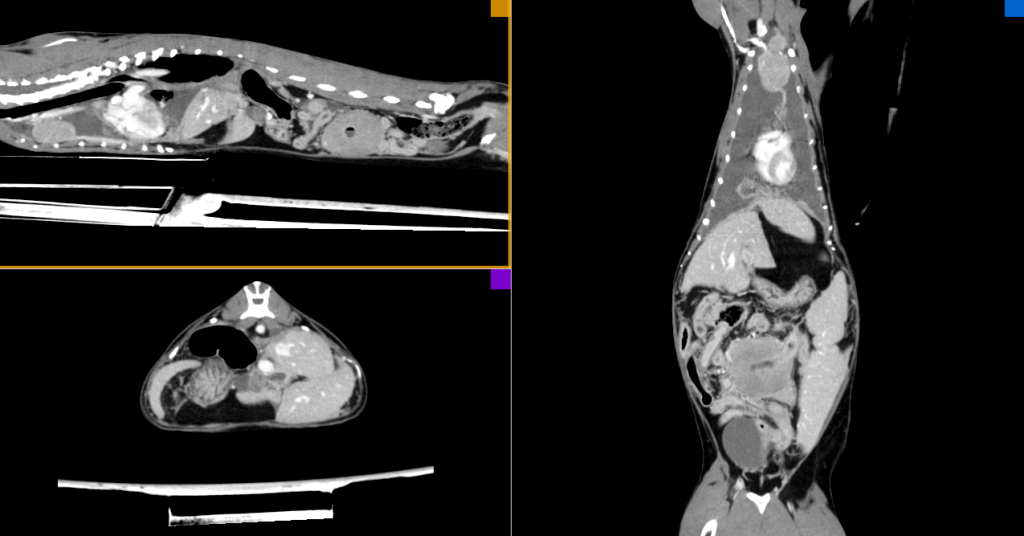

Неселективная КТ-ангиография (рис. 3) является одним из наиболее информативных методов диагностики опухолевых заболеваний у мелких домашних животных, она позволяет с высокой точностью определить зоны поражения, их анатомическое расположение, объем и связь с другими структурами организма пациента.

Описание результатов КТ. При проведении КТ у пациента было выявлено новообразование в краниальном средостении с иррегулярной формой и гетерогенной структурой, вовлекающее группу лимфатических узлов. На нативной серии плотность новообразования преимущественно изоденсивная, а его границы нечеткие.

После введения контрастного препарата отмечается его равномерное накопление преимущественно с гиперденсивной плотностью на контрастных и постконтрастных сериях. Границы между структурами лимфатических узлов остаются нечеткими, новообразование формирует единый конгломерат с ровными и гладкими краями. Значительные размеры новообразования (44,1 × 24,4 × 20,9мм) данного пациента привели к интимному прилежанию новообразования к легочному стволу и аорте. По данным КТ, также была обнаружена свободная жидкость в плевральной полости высотой до 25,2 мм с рентгенологической плотностью 13,9 HU.

Воздушность легких снижена, выявлены ателектазы краниальной доли левого легкого, вентральной части краниальной доли и средней доли правого легкого. Убедительных данных о наличии очагов патологической плотности, характерных для неопластического/метастатического поражения, не получено.

При исследовании брюшной полости методом неселективной ангиографии также была выявлена свободная жидкость высотой до 10 мм. Ткани сальника имеют признаки выраженного отека, печень выступает за край реберной дуги, сосудистый рисунок не обеднен, паренхима гомогенная. Отмечается выраженная гиперплазия мезентериальных лимфатических узлов, которая имеет схожие характеристики с лимфатическими узлами грудной полости.

Портальные лимфоузлы увеличены, имеют гетерогенную структуру и размеры 19,6 × 16,5 мм. Стенка кишечника утолщена до 3,9 мм, преимущественно в тонком отделе, активно накапливает контрастный препарат. Мезентериальные лимфоузлы увеличены, неоднородные по структуре, длина до 21,3 мм. В анатомическом расположении тощей кишки выявлено объемное новообразование (44,8 × 49,6 × 36,1 мм) с признаками сохранения просвета и толщиной стенки до 20 мм. Неопластический очаг имеет иррегулярную форму и гетерогенную массу, демонстрируя изоденсивную плотность на нативной серии и преимущественно гиперденсивную на постконтрастных сериях. Граница неопластического поражения на нативной серии нечеткая.

Заключение по результатам неселективной КТ-ангиографии:

- В проекции тощей кишки выявлены объемное образование (характерно для неопластического поражения, возможно, лимфомы), лимфаденопатия мезентериальных и портальных лимфоузлов (вероятнее всего, характерная для диффузного поражения), сопутствующие оментит и асцит.

- В краниальном средостении обнаружено объемное образование, что также характерно для неопластического поражения, наблюдаются гидроторакс и ателектаз долей легких.

- В краниальном полюсе левой доли щитовидной железы выявлено объемное образование, что может соответствовать неопластическому процессу.